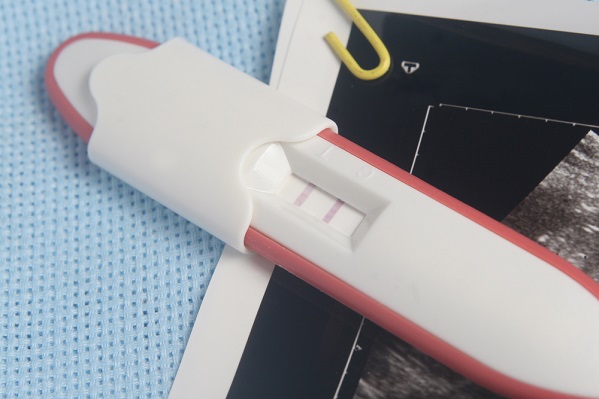

Untuk memastikan apakah terlambat menstruasi yang dialami termasuk ciri-ciri orang hamil tanpa mual atau bukan, Ibu bisa melakukan tes kehamilan. Terlebih jika Ibu memang memiliki siklus menstruasi yang tidak teratur.

Cara efektif untuk mengetahui apakah Ibu sedang hamil atau tidak selain dari munculnya rasa mual atau morning sickness yaitu dengan melakukan tes kehamilan. Tes kehamilan yang akurat dimulai sejak hari pertama Ibu telat menstruasi.

Jika Ibu tidak tahu kapan haid berikutnya, lakukan tes setidaknya 21 hari setelah terakhir kali Ibu melakukan hubungan seksual tanpa pengaman. Ibu bisa melakukan tes kehamilan sendiri dengan bantuan test-pack yang menggunakan sampel urin di pagi hari.

Meskipun Ibu merasakan salah satu dari ciri-ciri orang hamil tanpa mual di atas, Ibu sebaiknya melakukan tes kehamilan dengan bantuan tenaga medis untuk memperoleh hasil yang akurat.